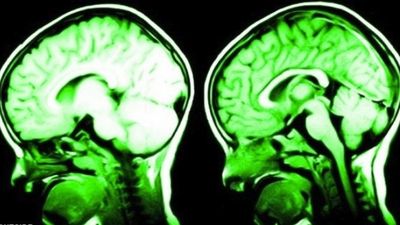

Gjërat të cilat e ndryshojnë fizikisht trurin, duke ju bërë juve më të mençur dhe pozitivë